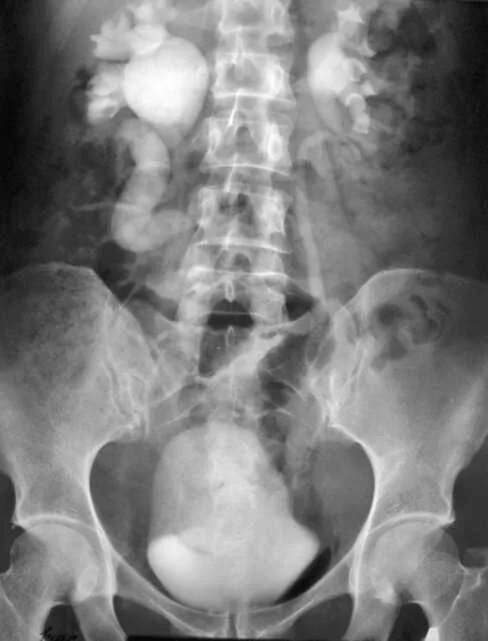

Урография с контрастом